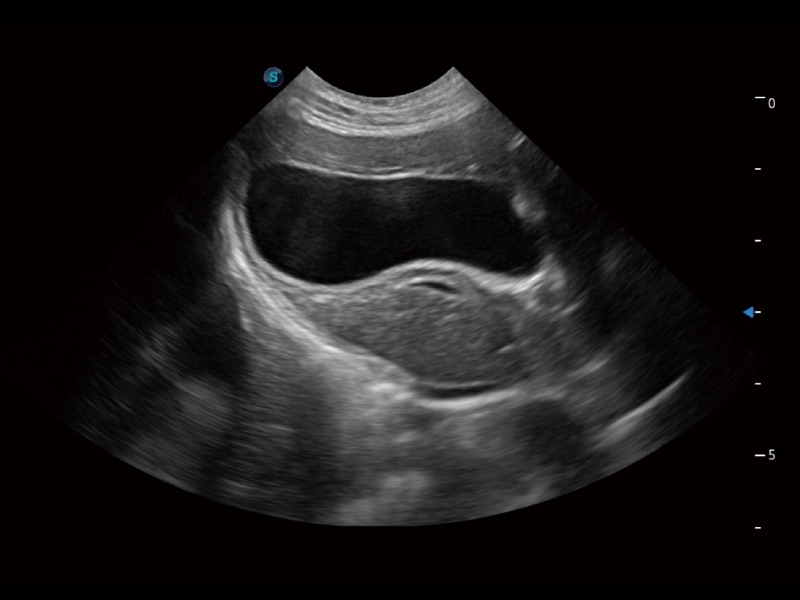

动物是人类最亲密的朋友和最值得信赖的伙伴。米兰官方网站也一直致力于探索动物专用的超声影像解决方案。全新推出的ProPet系列,是米兰官方网站在动物超声影像智能化、专业化、精准化的一次跨越式革新。动物不能用言语来表述自己的不适,通过超声影像,ProPet系列搭建了动物医生与不同物种沟通的“桥梁”,为动物医生注入了“治愈之力”。 ProPet 70将是您值得信赖的超声伙伴。它配备了复合材料线阵探头,帮助动物医生获得卓越精准的临床图像。同时ProPet 70直观便捷的操作体验以及专业的测量工具,可为不同体型和生理结构的动物带来全面临床评估,切实为动物医生提供智能、专业、精准的超声影像解决方案。

ProPet 70 进一步提升了微米成像算法,更加注重对基础原始图像的还原和保留,在有效减少斑点噪声、增强组织边界显示的同时,避免过度优化丟失真实的解剖信息。

ProPet 70专为动物医生设计,对不同的动物体型和生理结构作出了针对性的优化。通过动物影像专用软件,可满足个性化的应用需求,帮助动物医生获得更精确的诊断数据。

ProPet 70 全新的动物超声智能软件和丰富的探头群,为动物医生提供了高清晰度和精细分辨率的图像,无论在宠物、马科、畜牧还是实验室动物等应用中都可以轻松应对,为您的日常工作带来满意的体验。